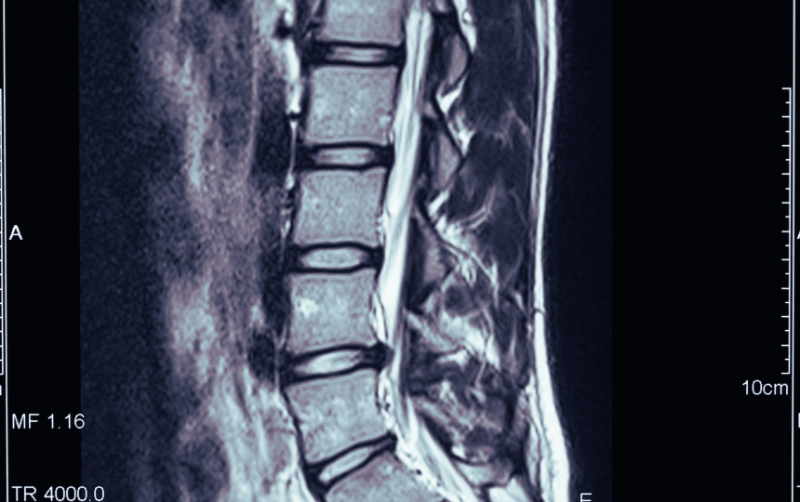

Présentation générale de la hernie discale lombaire

La hernie discale au niveau des lombaires est une affection courante du système vertébral qui affecte cette région de la colonne vertébrale. Elle survient lorsque le noyau gélatineux d'un disque intervertébral situé entre les vertèbres lombaires s'échappe de sa position normale, comprimant ainsi chaque nerf environnant.

C'est une condition courante de la colonne vertébrale caractérisée par la protrusion du noyau gélatineux d'un disque intervertébral. Dans le cas de la HD lombaire, cette protrusion se produit au niveau de la région lombaire du rachis. Les disques intervertébraux agissent comme des amortisseurs entre les vertèbres et, en cas de hernies, une partie des disques peut comprimer les nerfs spinaux adjacents. Cela entraîne souvent des souffrances lombaires intenses et, dans les cas graves, une irradiation dans les membres inférieurs.